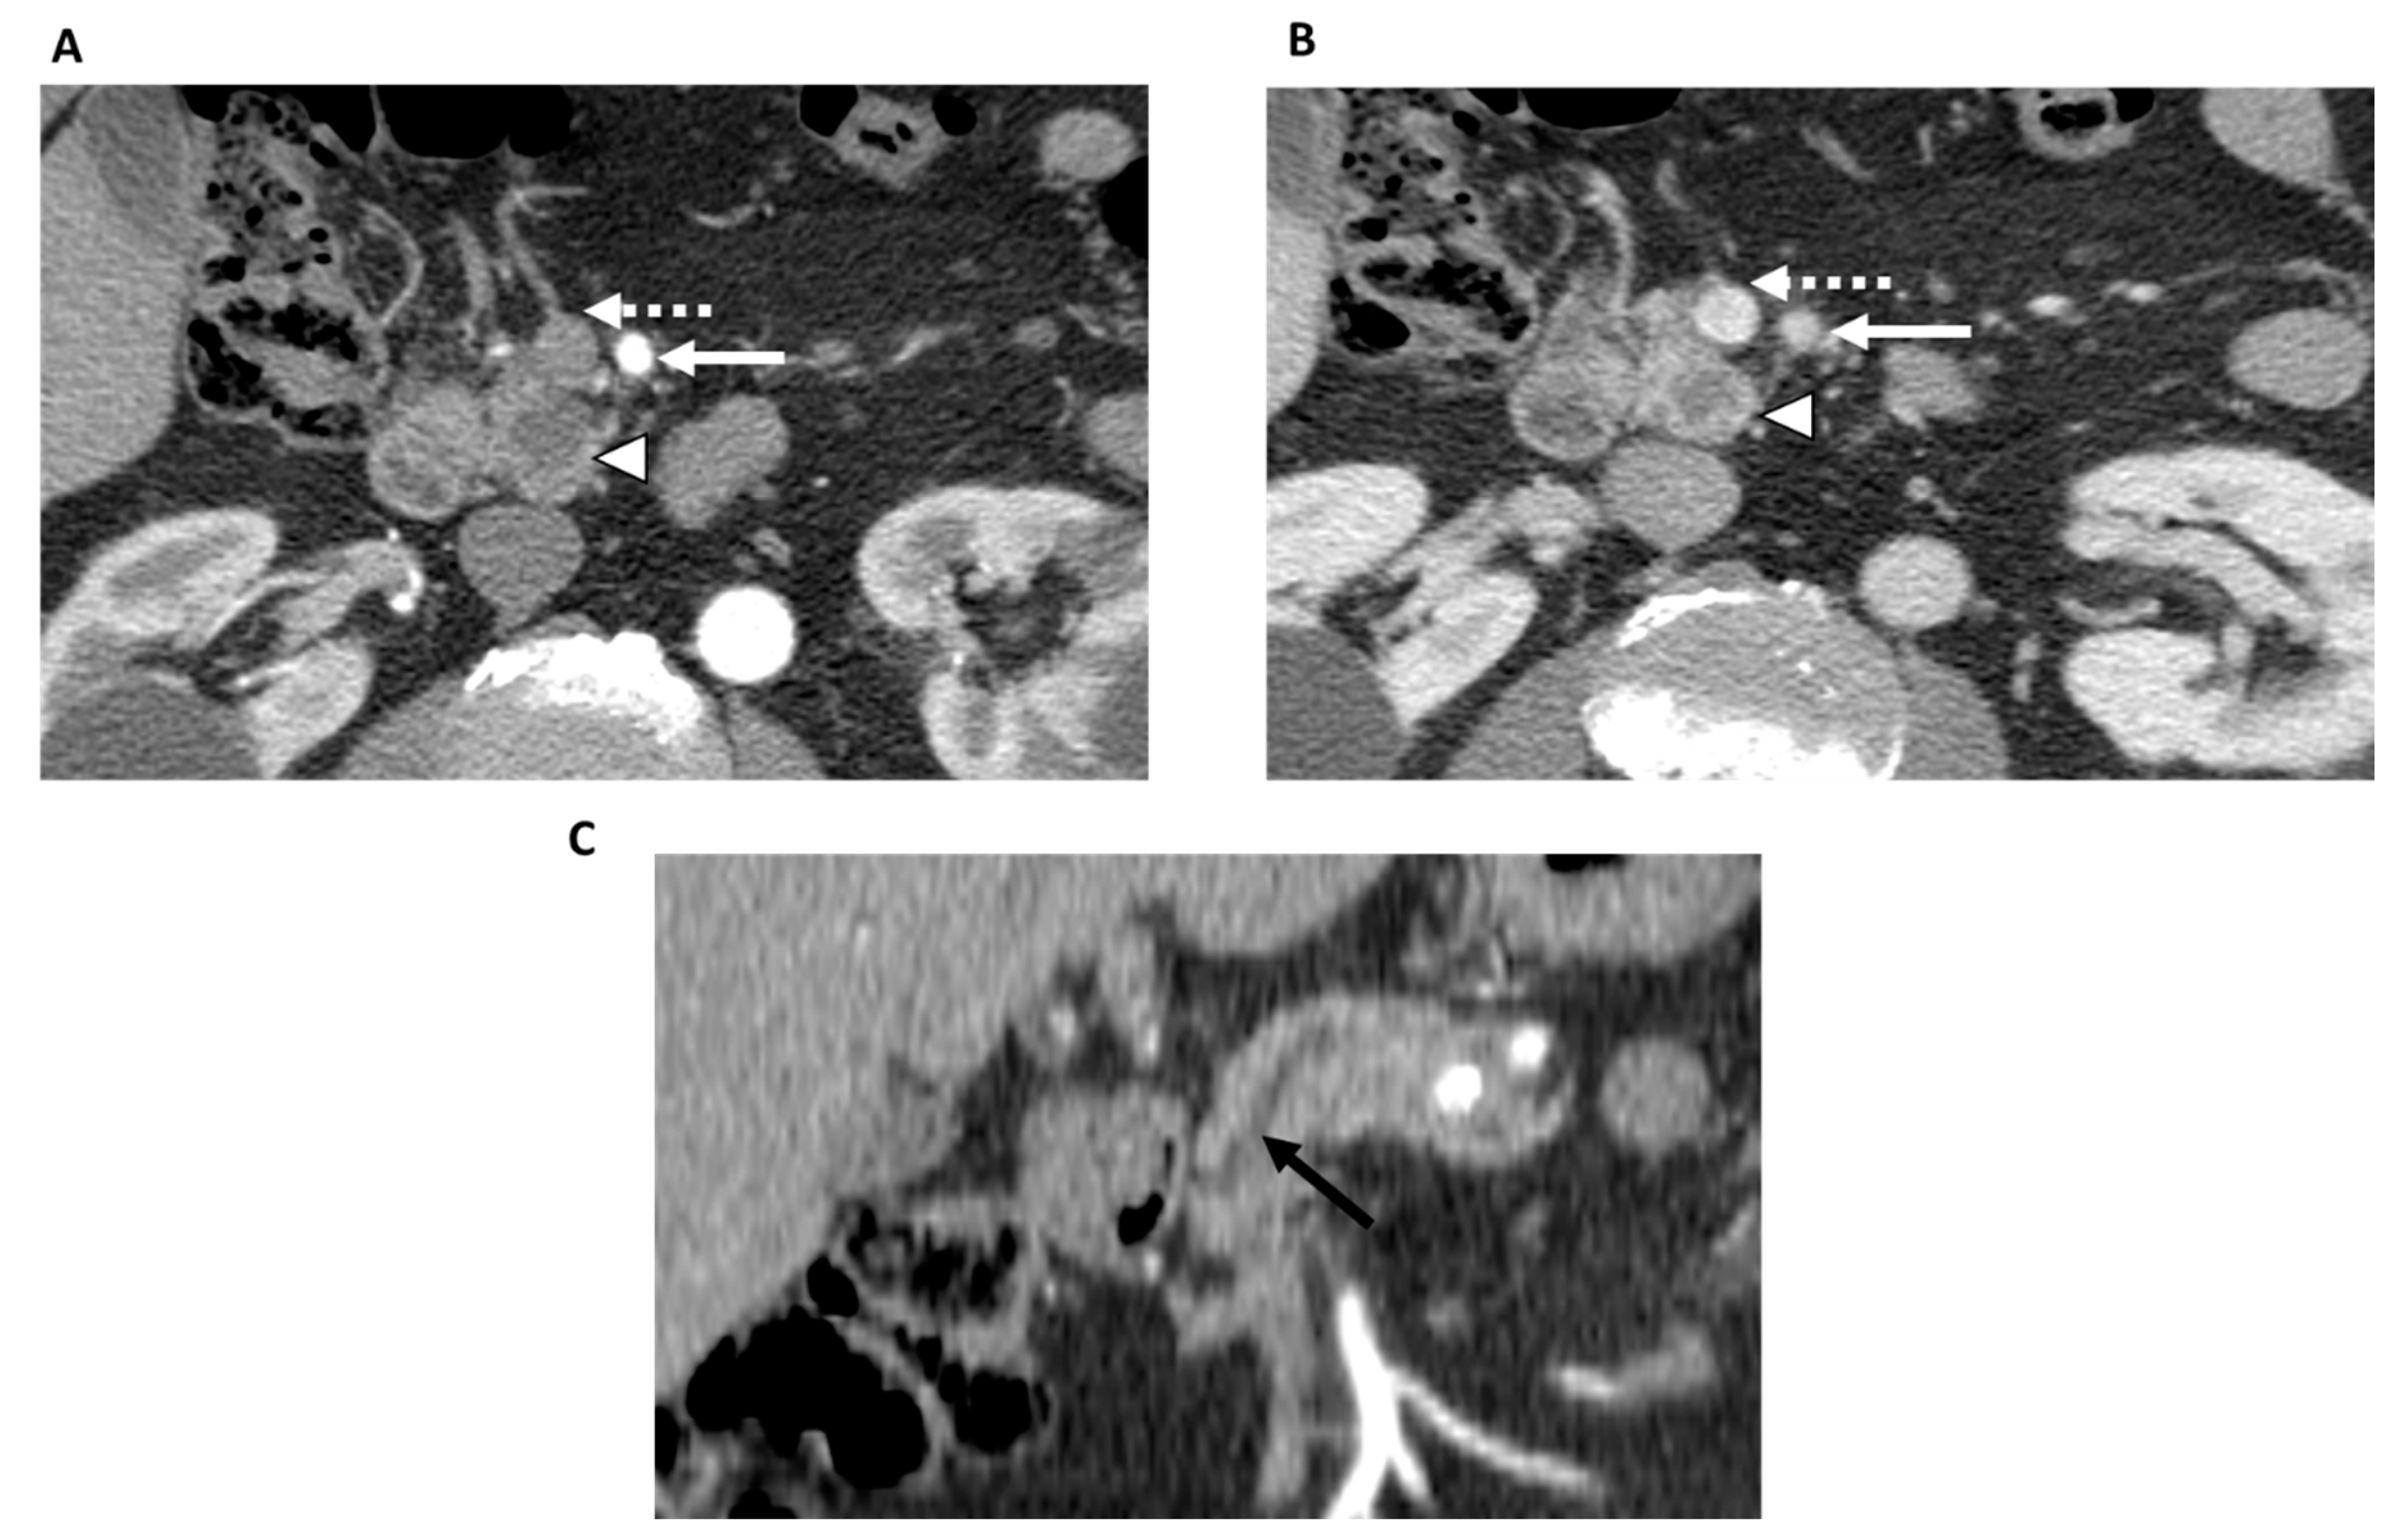

- Amer, A.M.; Zaid, M.; Chaudhury, B.; Elganainy, D.; Lee, Y.; Wilke, C.T.; Cloyd, J.; Wang, H.; Maitra, A.; Wolff, R.A.; et al. Imaging-based biomarkers: Changes in the tumor interface of pancreatic ductal adenocarcinoma on computed tomography scans indicate response to cytotoxic therapy. Cancer 2018, 124, 1701–1709. [Google Scholar] [CrossRef] [PubMed]

| Amer et al. [35], 2018 (U.S.) | 326 | -Response according to RECIST 1.1 criteria -Tumor/pancreas interface response developed by the authors | -Chemo -CRT | 3 radiologists | -Type I vs. Type II response at the interface was significantly associated with fewer viable cells after neoadjuvant therapy and was more likely to achieve major pathologic response (p = 0.01); Type I response also showed improved DFS and OS. |